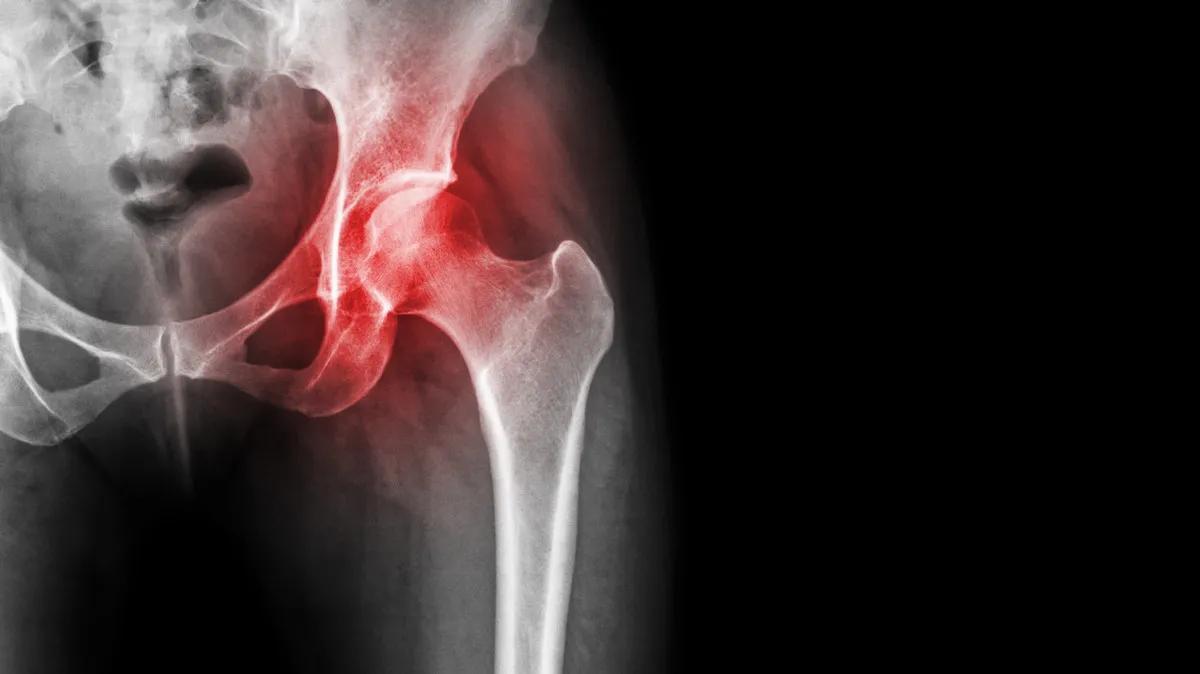

股骨头坏死是骨科常见疾病,发病的主要原因是股骨头供血不足,导致股骨头出现骨质疏松、病变,最终塌陷、坏死。

股骨头坏死的疼痛从哪来?

有人认为,疼痛是因为股骨头坏死引发了滑膜炎,关节腔里出现积液,造成了疼痛。

但这只是其中的一个原因,更主要的原因当股骨头供血不足,出现缺血坏死之后,股关节会承受的压力变得更大,而造成疼痛。

我们走路的时候,人体自身的重量会对股骨头造成挤压,力量从上往下传导的时候,在压力的作用下,它会产生微小的形变。

这时候如果关节软骨存在微骨折或者关节有炎症,使得关节腔有积液——要知道,关节里腔的积液没有办法往外排,这就导致了关节内部的压力会变大。

这时候当你站立或者行走,给股关节施加更大的压力时,高压就会刺激到神经感受器的末梢,产生疼痛的感觉。